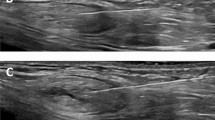

It is difficult to diagnose LNs after radiation therapy. Figure 1 demonstrates another case of a false-positive result; this is a hypopharyngeal cancer patient. He received an US exam 3 months after concurrent chemoradiotherapy. On US, multiple heterogeneous LNs above the carotid artery were found. US-FNA with the Sydney system was positive for malignancy. Preoperative US found lymph nodes with heterogeneous echo texture overriding the common carotid artery (Fig. 1A). On cytology, the smear showed a tumor necrotic debris background with some keratinocyte-like cells (in orange color) and some cell shadows with enlarged nuclei (in green color). This finding was comparable to malignancy in cytology according to the Sydney system (Fig. 1B). In the final pathology with H&E staining, calcifications, histiocytes, and necrotic debris with necrotic keratinocyte-like cells were observed (C: low power & D: high power). Because there were no viable carcinoma cells, the final diagnosis was no metastatic carcinoma.

There was one false-positive case in our study. Preoperative ultrasound found lymph nodes with heterogeneous echo texture overriding the common carotid artery (A). On cytology, the smear showed a tumor necrotic debris background with some keratinocyte-like cells (in orange color) and some cell shadows with enlarged nuclei (in green color). This finding was comparable to malignancy in cytology according to the Sydney system (B). In the final pathology with H&E staining, calcifications, histiocytes, and necrotic debris with necrotic keratinocyte-like cells were observed (C: low power & D: high power). Because there were no viable carcinoma cells, the final diagnosis was no metastatic carcinoma.